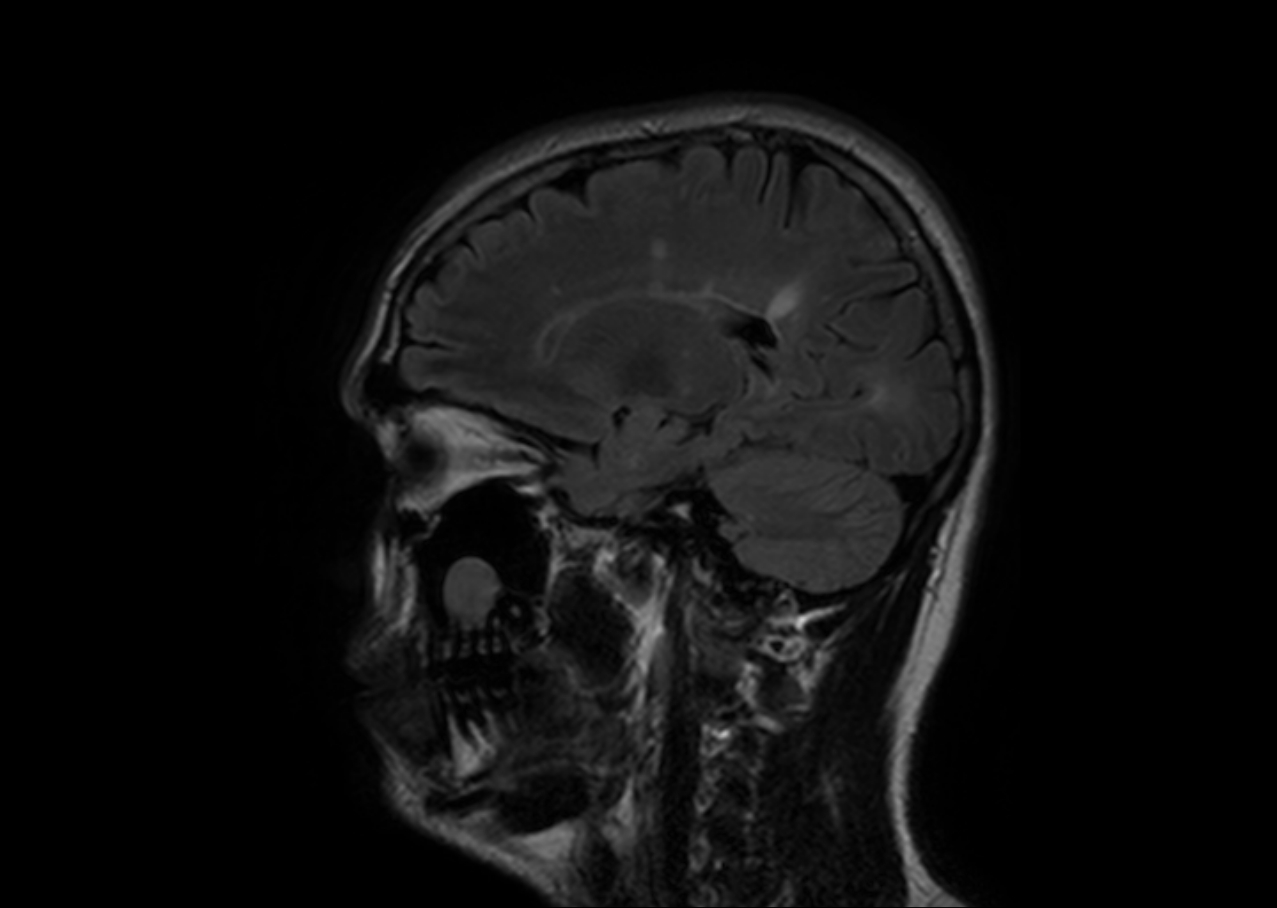

La esclerosis múltiple es una patología degenerativa cerebral que afecta las funciones psicológicas y físicas de quien la padece. Suele aparecer entre los 20 y 40 años de edad y se considera como la segunda enfermedad más frecuente en los adultos jóvenes, luego de la epilepsia. Solo en España cerca de 45 personas por cada 100.000 padecen esta patología.

En relación a sus causas aún no existe un patrón establecido. No obstante, los especialistas la relacionan con afectaciones del sistema autoinmune que, consecuentemente, provocan severas lesiones degenerativas y crónicas del sistema nervioso central.

Entre las afectaciones más comunes y unas de las primeras en percibirse se encuentra el proceso de desmielinización (la pérdida de la vaina de mielina que protege a los nervios y que facilita la transmisión de información cerebral) que provoca numerosos síntomas psicológicos y físicos como: hormigueo, rigidez muscular, fatiga, problemas en la coordinación, disminución de la atención y de la memoria, cambios en el comportamiento, entre otros.